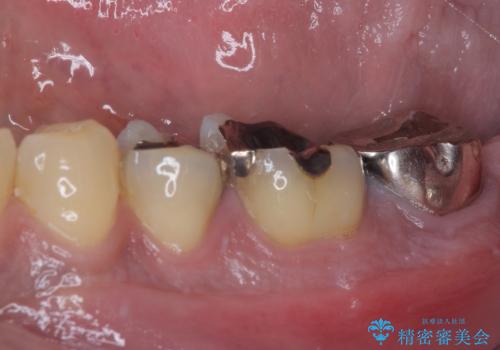

- 食事などで噛んだ時に奥歯が痛むとのことで来院された患者様です。

レントゲン写真より、一番奥の歯の根尖部に大きな病変(炎症により骨が溶けている状態)が認められたため、根管治療を行うこととしました。

根管治療後に痛みは一次消退しましたが、半年ほど経過しても病変は改善しておらず、歯根が破折している状態となっていました。

歯根が破折した歯は抜歯となるため、抜歯して病変の部分に骨が回復するのを待って、インプラントによる補綴治療を行うこととしました。